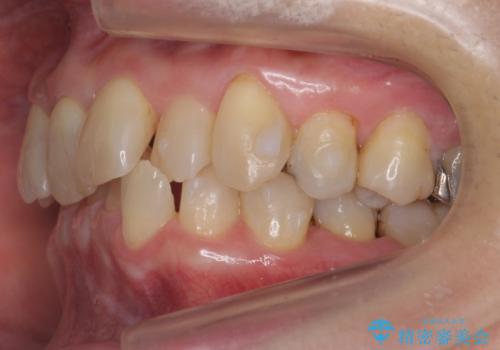

50代女性 インビザライン かみ合わせが深く、難しい症例

かみ合わせが深く、上の歯が咬みこんで下の歯にワイヤーがつけられない状態で、ワイヤー矯正はかなり難しい状態でした。

反対咬合や、すれ違い咬合もあり、大変難しいケースでしたが治療することができました。